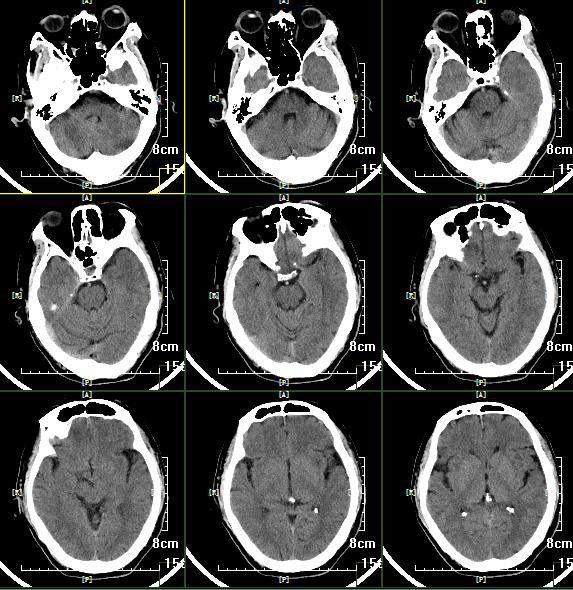

急诊头颅CT:颅内未见出血及大面积梗死。

术后即刻头颅CT

患者术后2周,复查头颅CT